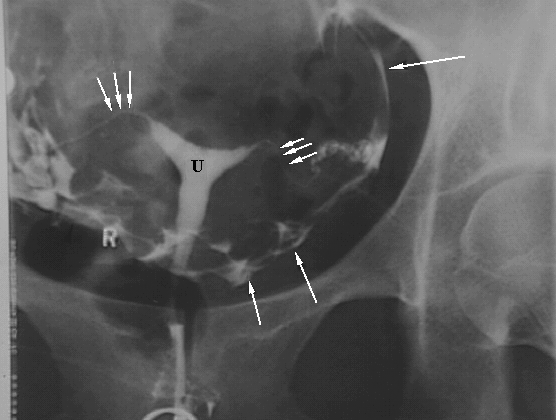

Pelvis & Perineum: Hysterosalpingiogram: